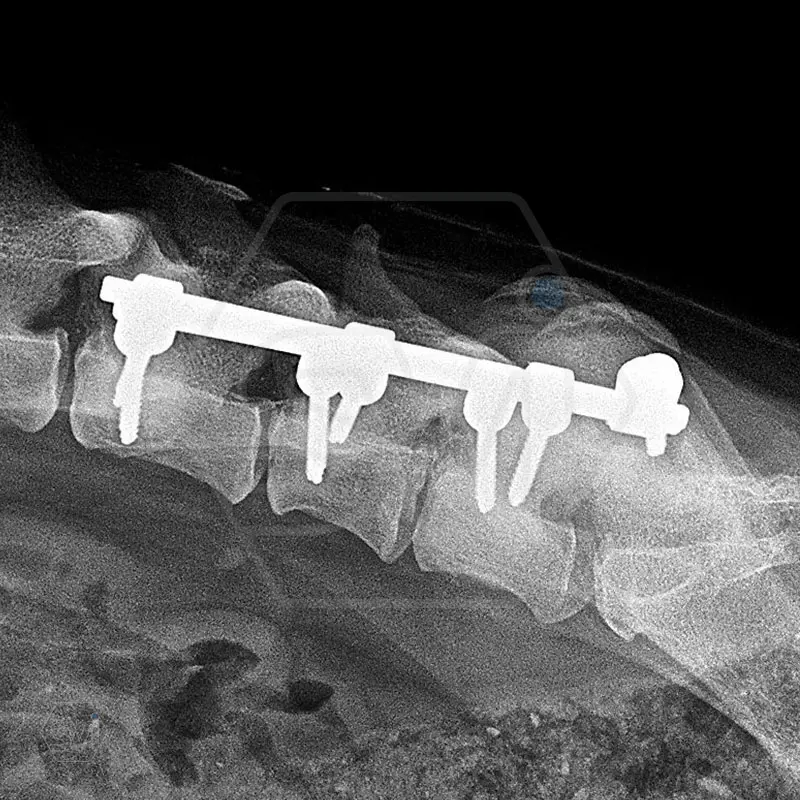

L6 vertebral body fracture fixation with 2.7-mm SOP-LC system

A mixed breed dog, 13 kg, about 8 months old, suffered a car accident and had a fracture of the L6 vertebral body with a mild displacement. (As an additional finding, there was also a fracture of the right radius ulna.) After the accident, his neurological condition was promising.

We performed a laminectomy of L7 and then performed fixation with a 4-4 clamp, bilateral 2.7-mm SOP-LC system. Control x-rays were taken at 6 and 12 weeks after surgery. Based on the video, in our opinion, the dog has recovered… :)